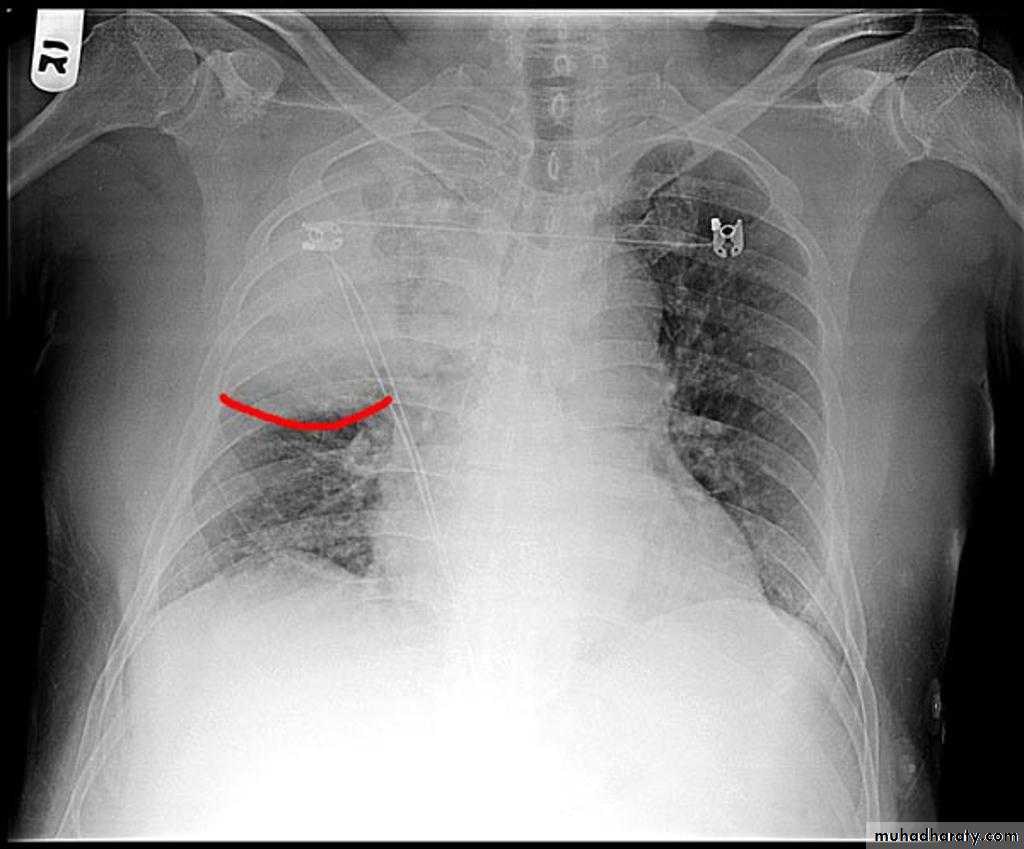

Homogenus opacity of the left hemithorax with shifting of the trachea to the same sidePleural effusion

Homogenus opacity of right lower zone with meniscus signOblitration of right cardiophrenic and costophrenic angles

Homogenus opacity of the right hemithorax

Oblitration of cardiophrenic and costophrenic angles

Shifting of the trachea to the opposite side

Pleural effusion

Homogenus opacity of right lower lobe with Oblitration of right cardiophrenic and costophrenic angles.

Meniscus sign